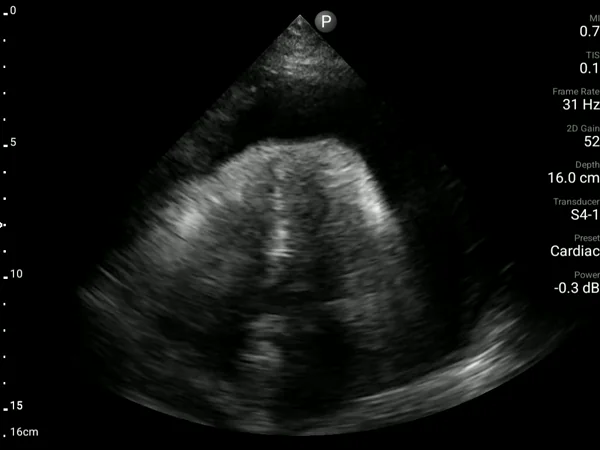

A 89-year-old man with congestive heart failure and a TAVI performed four months earlier presented with shortness of breath and desaturation. A bedside AISAP exam revealed EF 18%, severe MR, severe TR, and an enlarged right atrium.A formal echocardiogram confirmed these findings, and he was referred for MitraClip as part of his comprehensive management plan.